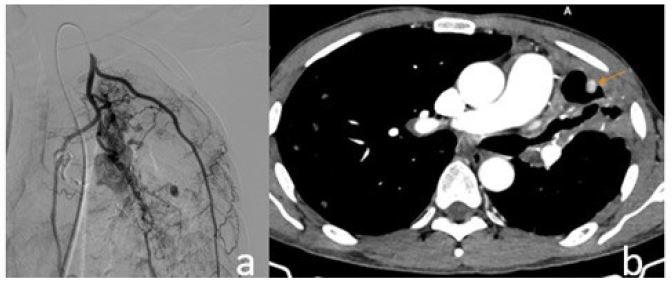

Subsequently, the patient was referred for CT-guided percutaneous intervention. Under CT guidance, an 18G needle was advanced into the pseudoaneurysm, and contrast injection verified intraluminal positioning. Embolization was performed with NBCA: lipiodol at a 1:2 ratio. Post-procedural contrast-enhanced CT demonstrated complete filling of the pseudoaneurysm sac with glue, indicating successful occlusion. The patient experienced no further hemoptysis and was discharged after 4 days, with initiation of standard anti-tuberculosis therapy.

Figure 4: (A) CT-guided intervention with an 18G needle puncturing the pseudoaneurysm, followed by injection of NBCA glue mixed with lipiodol at a 1:2 ratio. (B) Post-procedural assessment shows complete occlusion of the pseudoaneurysm. A small amount of glue is seen refluxing into a minor branch of the pulmonary artery. Clinically, the patient had no further episodes of hemoptysis.

Was the pseudoaneurysm observed in the above clinical case truly a Pulmonary Artery Pseudoaneurysm (PAP)? The absence of a pseudoaneurysm on DSA of the left pulmonary artery does not entirely exclude its presence, especially given its peripheral location and small size. The affected branches exhibited wall damage, anatomical complexity, and altered flow dynamics, which hindered successful selective catheterization. Upon successful direct puncture of the pseudoaneurysm, NBCA glue was observed to pool in a focal area and reflux into a small pulmonary arterial branch, indicating retrograde flow and confirming communication with the pulmonary circulation.

In situations where endovascular access fails or is anatomically unfeasible, percutaneous puncture techniques may be considered, although they carry inherent risks such as pneumothorax or pseudoaneurysm rupture if not performed with precision [3,6]. In the reported case, the initial attempt at direct puncture under DSA guidance failed and resulted in a temporary recurrence of hemoptysis. Subsequently, CT-guided intervention allowed for precise localization of the pseudoaneurysm and accurate delivery of glue, achieving definitive therapeutic success. Using a higher NBCA-to-lipiodol ratio (1:2) increased the mixture’s viscosity, limiting glue dispersion and reducing the risk of non-target embolization.